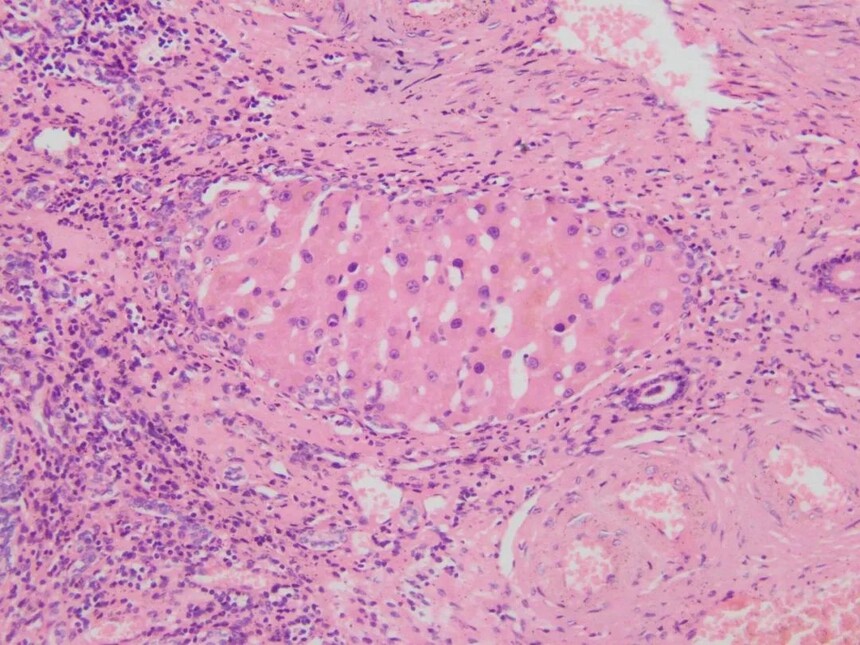

9、风湿性心肌炎

心肌组织切片可见心肌间质水肿,伴炎症细胞浸润,在心肌间质小血管旁可见梭形或不规则形风湿小体,风湿小体中心有红染无结构的纤维素样坏死物,周围是体积肥大、胞浆丰富、略嗜碱性、核圆形或卵圆形的风湿细胞,风湿小体周围有少量单核细胞、淋巴细胞和浆细胞浸润。风湿细胞核的染色质聚集在中央城毛虫状或枭眼状。